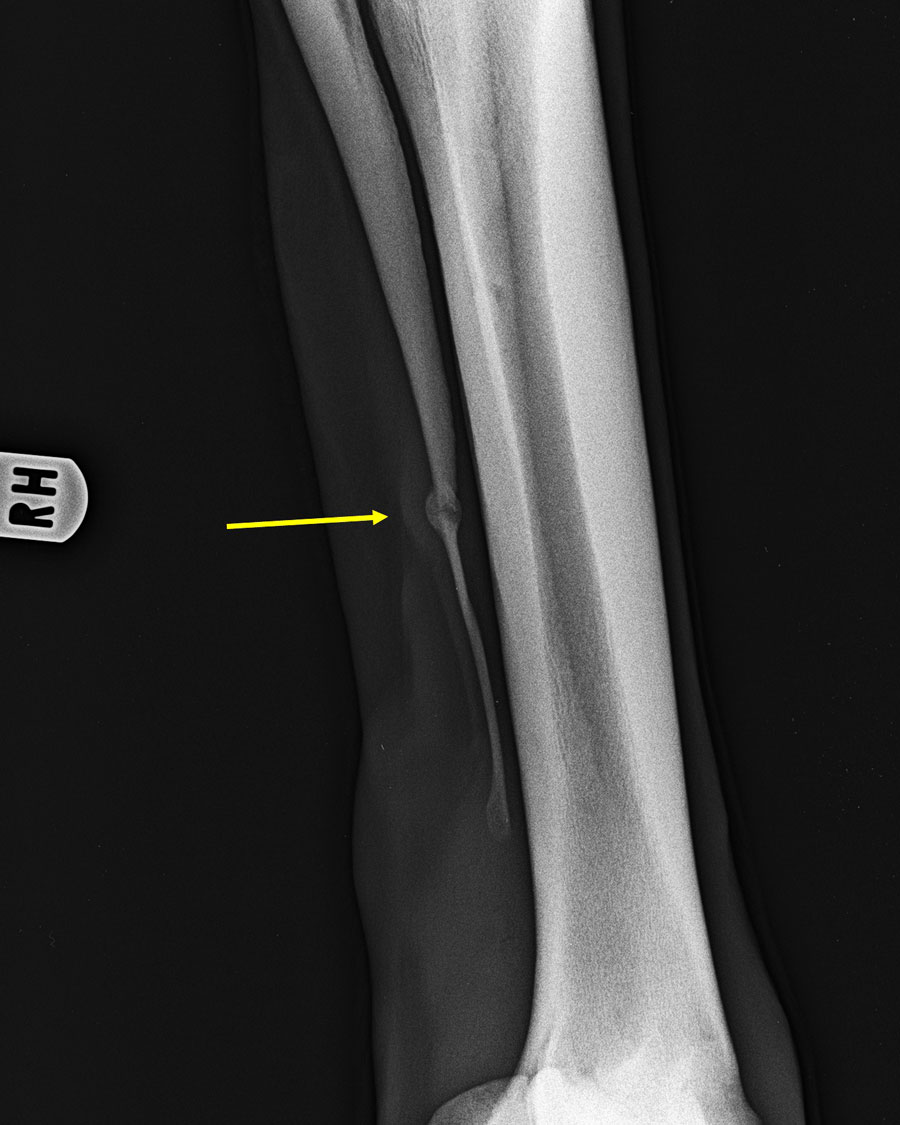

Griffelbeinfraktur vor 7 Wochen durch Schlagverletzung